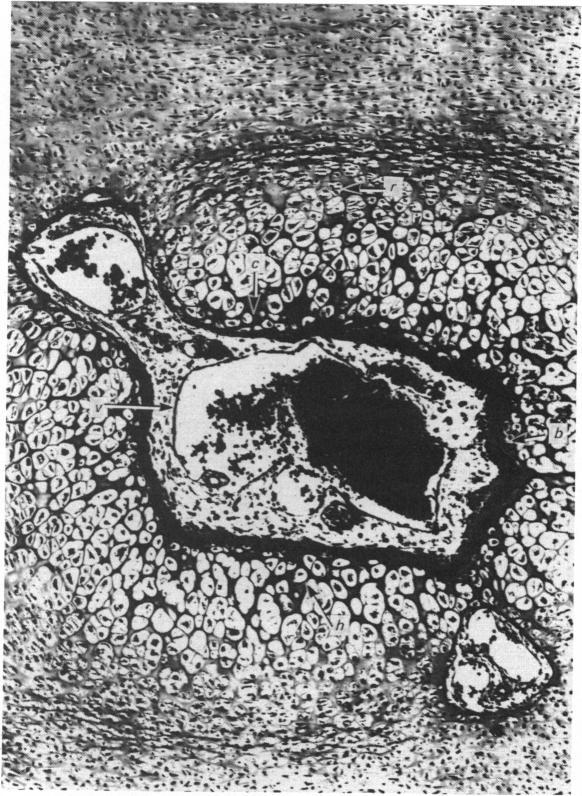

Bone formation in the vertebral centra commences within the centrum and is in this respect analogous to the secondary ossification which occurs in the epiphysis of a long bone. Bone tissue first appears at about the 85 mm C.R. stage and not in the 55 mm C.R. length embryo; at the latter stage blood vessels and calcification alone were observed. The connective tissue cells within the cartilage canal appear to assist osteogenesis by providing osteogenic cells which lay down bone in the walls of the cartilage canal, and provide cells which remove calcified cartilage found at the periphery of the canal; they assist growth by producing an appreciable number of chondrocytes that permit lateral expansion of the centra. Osteogenesis appears to occur in multiple foci within the growth plate of the older embryos and could account for the rapid rate of growth of vertebrae. Bone formation occurs in both mineralised and unmineralised matrix (as seen on the walls of the cartilage canals). The blood vessels within the growing vertebra tend to follow the zone of cartilage hypertrophy.